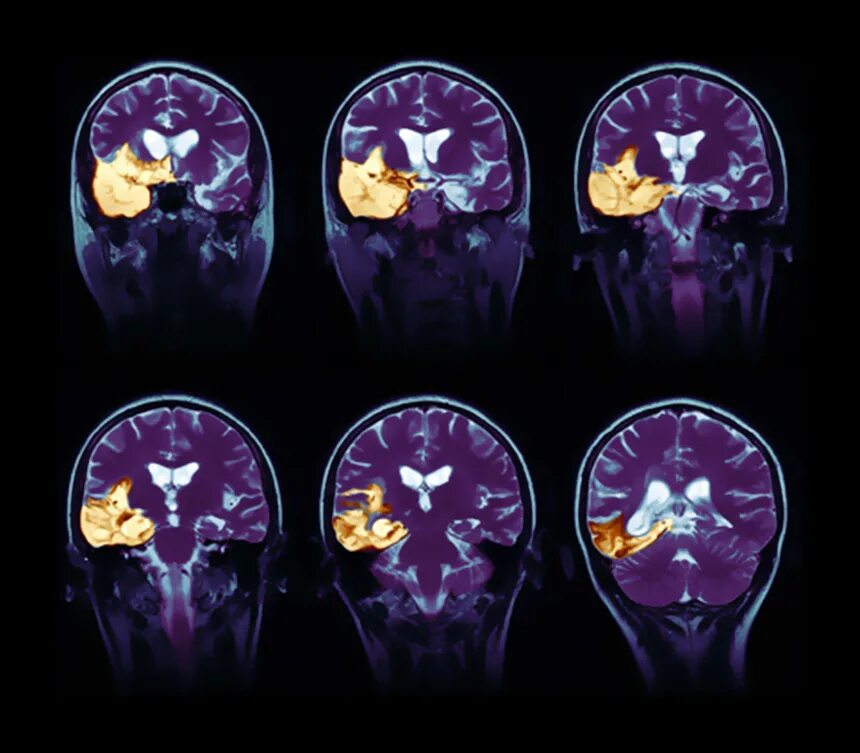

Энцефалит головного мозга симптомы у взрослых